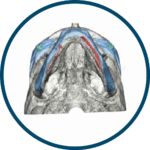

OMNIPORE® de Matrix Surgical es un implante poroso de alta densidad diseñado para reconstrucción cráneo-facial y cirugía estética. Fabricado en polietileno poroso, permite ser fresado, cortado o moldeado durante la cirugía para una adaptación precisa a la anatomía del paciente. Su estructura favorece el crecimiento tisular, promoviendo una mejor integración y estabilidad a largo plazo. Se suministra estéril y listo para su uso inmediato, evitando riesgos de contaminación al no requerir reesterilización.